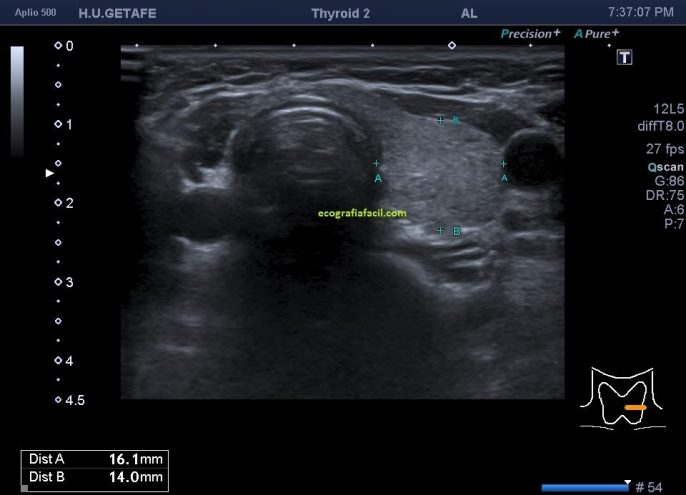

En ocasiones nos encontramos la imagen 2 (disgenesia) que te muestro a continuación y que quiero que estudies y compares con la imagen superior.

En este micropost número 3 dedicado al tiroides tienes una ausencia de uno de los lóbulos tiroideos (hemiagenesia), en concreto del lóbulo tiroideo derecho.

cuando encontramos estos hallazgos estamos ante dos posibilidades, una cirugía previa de la paciente donde se le hubiese retirado quirúrgicamente uno de los lóbulos (hemitiroidectomía), habitualmente por la presencia de bocio multinodular (ya que cuando un paciente es diagnosticado de ca. de tiroides, se realiza tiroidectomía total y no parcial), la otra posibilidad es una agenesia tiroidea, es decir, una ausencia congénita de parte de la glándula tiroides.

Si es una cirugía, normalmente lo sabremos puesto que el médico peticionario nos lo habrá indicado en su petición y veremos una cicatriz.

Si no hay cirugía previa el paciente puede desconocer el echo de que le falte una parte de su glándula, con lo cual deberemos preguntar si tiene cirugía previa del tiroides, normalmente responderá negativamente y entonces sabremos que la ausencia tiroidea se debe a una anomalía congénita, tal caso debemos comentarlo a la radióloga.

En la imagen 3 y 4 te muestro el desarrollo del estudio normal en esta mujer de 63 años que no tenía ni idea de la ausencia congénita del lado derecho de su tiroides, representado en el corte longitudinal con la imagen 5 donde encontramos «nada» donde debería estar una ecoarquitectura similar a la imagen 4.